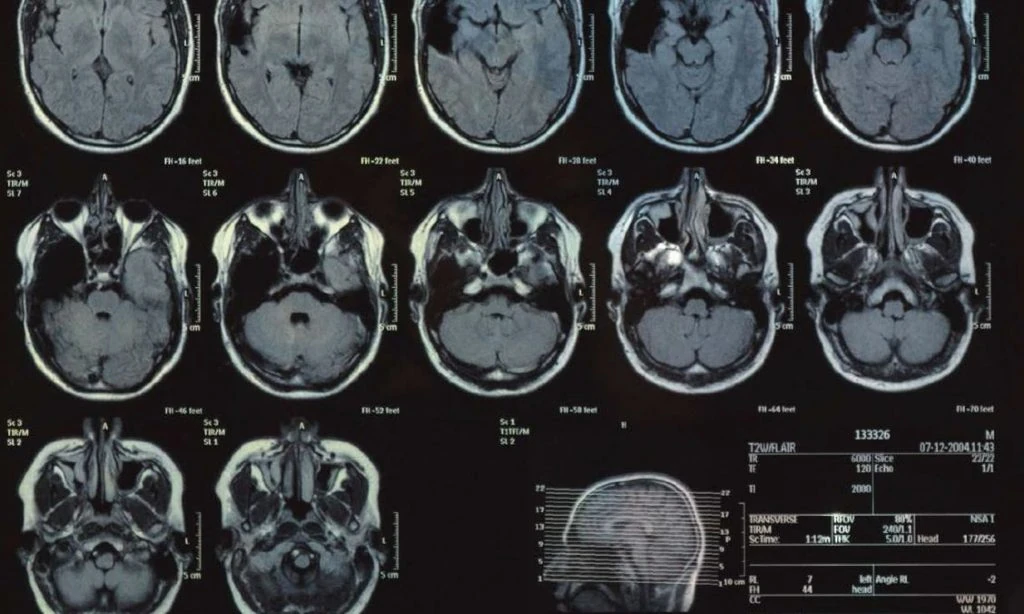

پس از آنکه یک توده در مغز از طریق روشهای تصویربرداری مانند MRI شناسایی شد، قدم بعدی برای تشخیص قطعی، نمونهبرداری از بافت تومور است. هرچند تصویربرداری میتواند اطلاعات ارزشمندی در مورد اندازه و مکان تومور بدهد، اما نمیتواند ماهیت سلولی آن را مشخص کند. این فرآیند که بیوپسی (Biopsy) نامیده میشود، سنگ بنای تعیین گرید تومور است.

- گریدهای پایین (۱ و ۲): برای تومورهای گرید ۱، جراحی کامل اغلب به معنای درمان قطعی است و نیاز به درمان دیگری نیست. برای تومورهای گرید ۲، جراحی برای برداشتن حداکثر توده ممکن، اولین قدم است. پس از جراحی، بسته به عواملی مانند میزان باقیمانده تومور، علائم بیمار و ویژگیهای مولکولی، ممکن است رویکرد تحت نظر گرفتن فعال با MRIهای منظم اتخاذ شود یا در برخی موارد، رادیوتراپی یا شیمیدرمانی نیز برای به تأخیر انداختن عود بیماری توصیه گردد.